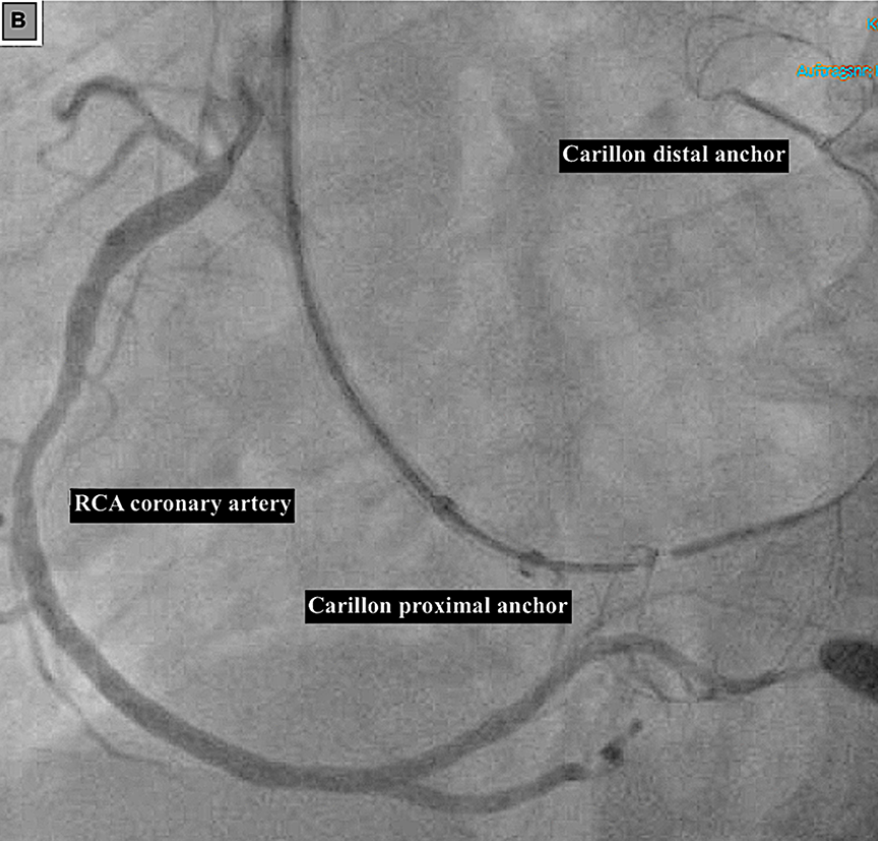

(三)Carillon装置经导管间接二尖瓣瓣环成形术的距离

利用Carillon装置行冠状窦为基础的间接二尖瓣瓣环成形术时,LCX受压或闭塞是已明确的并发症,操作中需格外谨慎以避免该损伤。一项纳入25例患者的回顾性心脏CTA分析研究明确了LCX受损的预测指标:装置远端着陆区的冠状窦-LCX距离<8.6mm时,LCX受损的风险显著升高,该指标为术前评估提供了量化依据。

临床心绞痛症状、心电图变化和术中冠脉造影可帮助诊断LCX受损,治疗策略需个体化:重新定位Carillon装置;更换治疗策略(如经导管缘对缘修复Mitral Clip);LCX支架植入;无症状患者可选择保守治疗。

冠状动脉与Carillon装置植入的关系

(A)冠状动脉造影显示Carillon装置植入后回旋支冠状动脉边缘支存在明显狭窄。(B)冠状动脉造影显示右冠状动脉从Carillon装置旁走行。